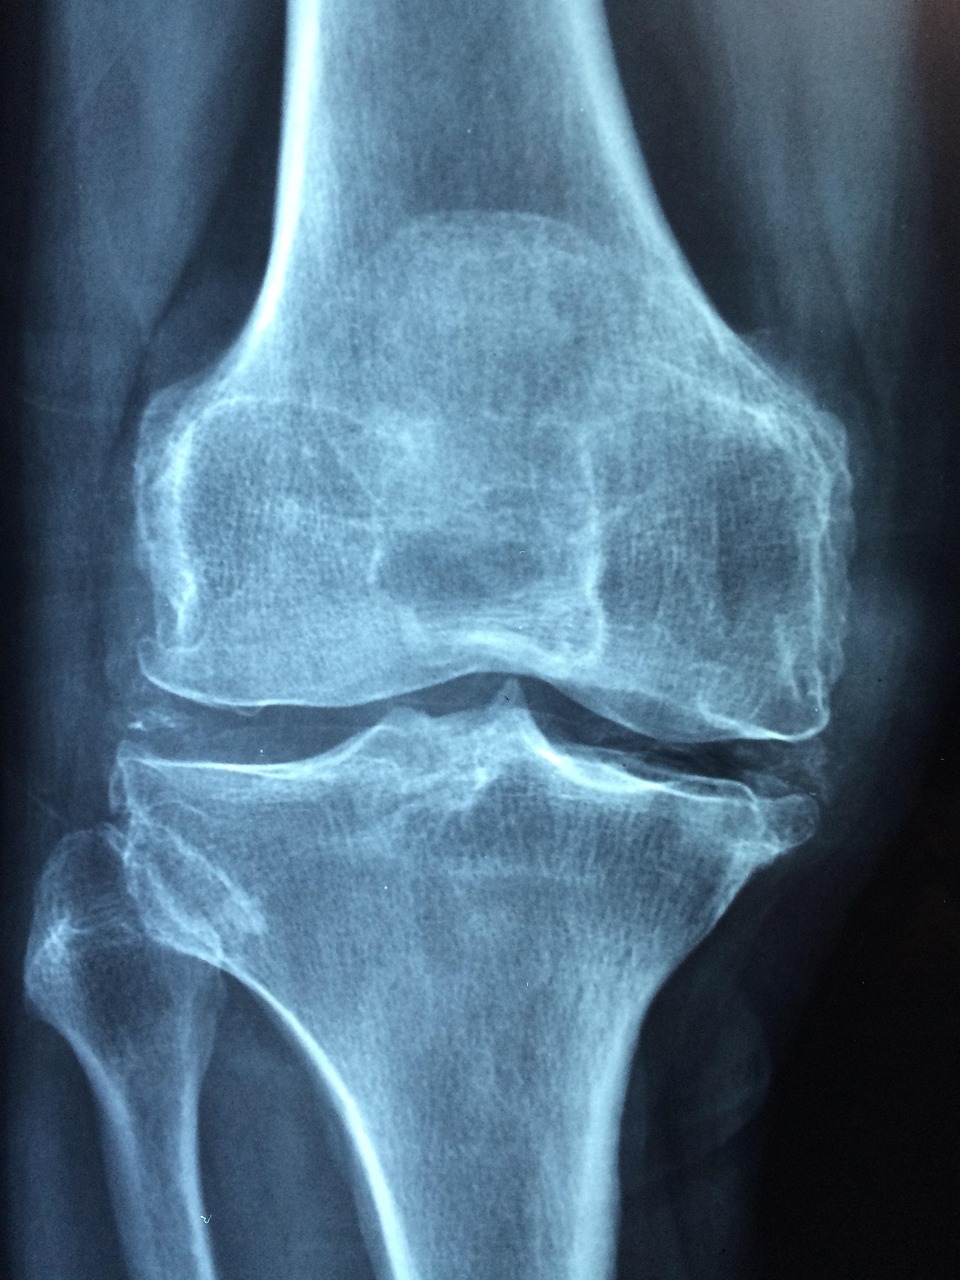

관절염 예방은 단순히 운동과 식단 관리만으로는 완성되지 않습니다. 일상 속 작은 습관의 차이가 장기적으로 관절 건강에 큰 영향을 미칩니다. 첫째, 올바른 자세 유지가 중요합니다. 오랫동안 다리를 꼬고 앉거나 허리를 구부정하게 세우는 자세는 관절에 불필요한 압력을 줍니다. 특히 장시간 앉아 있는 직장인이라면 1시간마다 일어나 간단한 스트레칭을 하거나 체중을 분산시킬 수 있는 자세를 취하는 것이 좋습니다. 또한 무거운 물건을 들 때는 허리가 아닌 무릎을 굽혀 들어야 허리와 관절에 무리가 덜 갑니다. 둘째, 수분 섭취는 종종 간과되지만 매우 중요한 요소입니다. 관절은 윤활액을 통해 원활하게 움직이는데, 수분이 부족하면 윤활 기능이 떨어져 관절 마찰이 증가합니다. 이는 통증과 염증의 원인이 될 수 있으므로 하루 1.5~2리터의 물을 나누어 마시는 습관을 들이는 것이 필요합니다. 셋째, 스트레스 관리 역시 관절 건강에 영향을 줍니다. 스트레스가 쌓이면 몸에서 염증 물질이 분비되어 관절염 증상을 악화시킬 수 있습니다. 요가, 명상, 심호흡, 가벼운 산책 같은 활동은 정신적 안정뿐 아니라 신체 건강에도 긍정적입니다. 마지막으로, 정기적인 검진과 조기 치료 습관을 강조해야 합니다. 관절염은 초기에 발견하면 생활습관 관리만으로도 진행을 늦출 수 있습니다. 그러나 방치하면 연골 손상이 심해져 수술까지 필요할 수 있습니다. 따라서 평소 관절에 잦은 통증이나 붓기, 열감이 느껴진다면 지체하지 말고 전문의를 찾아 정확한 진단을 받는 것이 현명합니다.